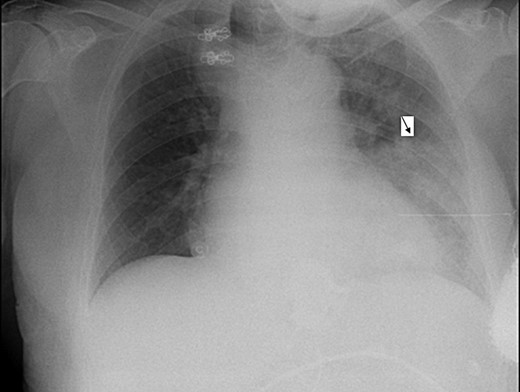

Electrocardiogram was remarkable for Q waves in leads I, aVL and V6. Chest X-ray (CXR) demonstrated a marked esophageal distention with an air fluid level (Figs 1 and 2).

Anterio-posterior CXR views demonstrate the shadow of a dilated esophagus and air fluid level (black arrow).